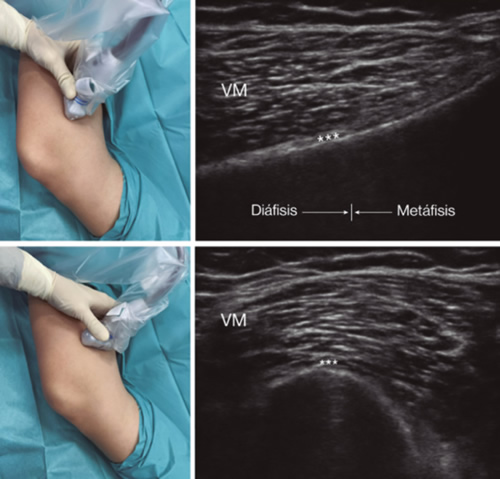

Para lograr una correcta ubicación de las referencias anatómicas por ultrasonido debemos colocar al paciente en posición supina con la rodilla flexionada y una almohada debajo de la fosa poplítea (14,16,19). Después de realizar asepsia/antisepsia de la rodilla, colocación de campos quirúrgicos y de la funda estéril del transductor lineal de alta frecuencia, procedemos a ubicar el NGSM (Figura 3). Colocando la sonda en un plano coronal sobre la cara interna de la rodilla, la deslizamos en sentido craneal hasta visualizar la unión de la metáfisis con la diáfisis femoral y la arteria/nervio geniculado superomedial (ANGSM), usualmente están localizados cerca al periostio del fémur (en caso de no encontrar esta estructura neurovascular, se toma como referencia la unión de la metáfisis y la diáfisis femoral). Después se marca en la piel el punto medio del transductor que corresponde a la ANGSM y se gira el transductor para ubicarlo en el plano transversal o axial para visualizar la ANGSM en eje corto (si no es posible la visualización de esta estructura, confirmar que estamos a un 50 % de la profundidad del fémur). En este corte transversal se avanza la aguja de RFT en plano desde anterior a posterior hacia la ANGSM o hasta una profundidad del 50 % del espesor del fémur. Finalmente se vuelve a girar el transductor 90°, dejándolo en un plano coronal para comprobar que la punta de la aguja está cerca de la ANGSM o de la unión de la metáfisis y la diáfisis femoral (14,16,19).

Fig. 3. Sonoanatomía y técnica para realizar el bloqueo del nervio geniculado superomedial (NGSM). El transductor se ubica en el eje largo distal del fémur y una vez que se tenga la posición del NGSM (asteriscos), se gira la sonda 90 grados para obtener una visión en eje corto del fémur (no olvidar mantener la misma profundidad a la que encontramos el NGSM en el eje largo). VM: vasto medial.